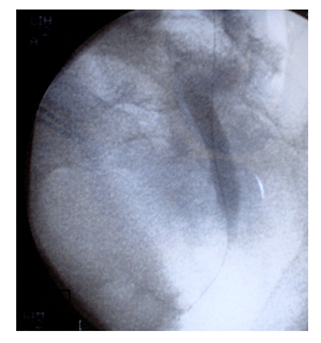

All procedures were carried out under general anesthesia. The patient was placed in the modified supine position. The flank is elevated 30 to 45° with regard to horizontal plane and lower limbs are split and bent in a lower position (Figure 1). The retrograde approach was used initially in all cases. If unsuccessful (Failure to find ureteric orifice or Failure to cross stricture), antegrade or both antegrade and retrograde approach was attempted. The most accessible posterior calyx was punctured under ultrasound guidance using a 22G Chiba needle and the tract dilated to 10 Fr. Radiopaque contrast and Methylene blue were injected into the renal cavity. The renal pelvis, Pelviureteric junction and calyces were identified as the seat and length of the stricture (Figures 2A & 2B). Once the pelviureteric junction was crossed and the ureter accessed, a straight hydrophilic guide wire and a special intrarenal manipulation catheter were used to cross the malignant ureteric stricture (Figure 3). If the stenosis was too tight and that the guide failed to pass, a resection guided with fluoroscopy in the direction of the guide was performed in the same flank modified position. The resection was continued until visualization of the guide and Methylene blue.

Figure 2 A: Identification of the renal pelvis, pyeloureteral junction and calyces and kidney access.

B: Identification of the stenosis and its length.